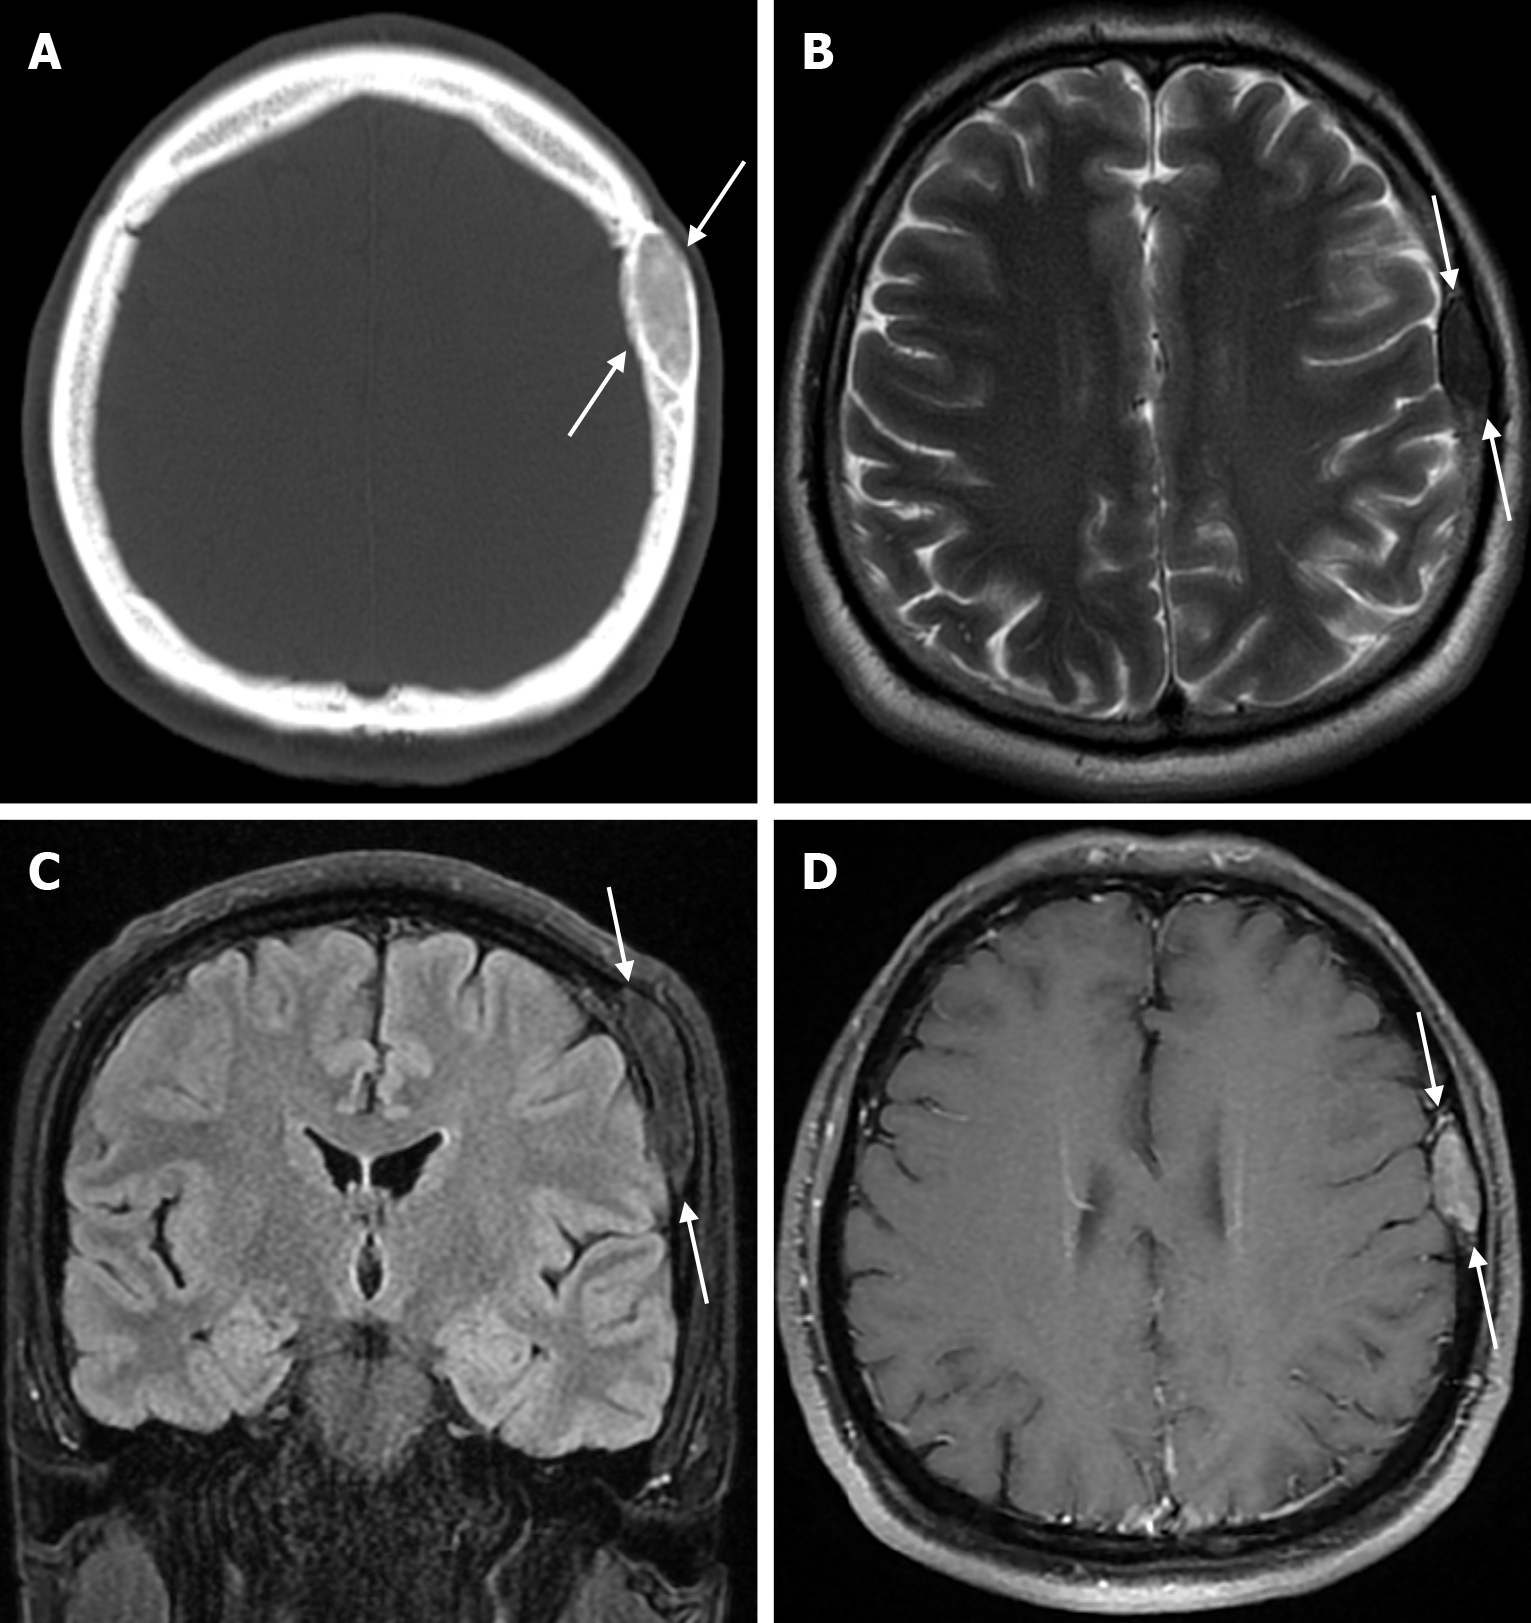

The transcalvarial venous channels are the openings in the calvarium that connect the dural venous sinuses to the extracranial veins via emissary veins. They are usually seen as serpentine or linear lucencies with sclerotic margins along the skull, and when these vessels are dilated they are known as venous lakes. Venous lakes are sometimes confused with fractures or sutures[14]. Venous lakes are present in about 15% of patients and are not associated with age or gender[15]. Venous lakes appear on CT as round or oval lucencies at the level of the skull base (Figure 3). On MRI, they show medium or low signal intensity on T1-weighted images, high signal on T2-weighted images, and significant contrast enhancement is seen in contrast-enhanced series[14]. It is important to distinguish venous structures from metastases. Metastases often show restricted diffusion within the lesion due to high cellularity. In addition, metastases may show increased blood flow within the lesion. Metastases often invade adjacent tissues[15].

Epidermoid cysts are small or medium-sized, benign, and slow-growing tumors that arise from the remnants of ectodermal cells in the bones of the skull. These cysts can also develop after trauma or surgery. Epidermoid cysts are lined with squamous epithelium. They contain deposits of cholesterol and keratin. These cysts constitute less than 1% of primary intracranial tumours, while intradiploic epidermoid cysts account for less than 0.25% of intracranial tumours. These tumors can occur at any age from the first decade of life to the seventh decade, with a mean age of 32-38 years, and there is no gender predilection. Epidermoid cysts are most commonly found in the frontal, parietal and occipital regions and often involve more than one bone. Epidermoid cysts appear on plain radiography as round or lobulated lytic areas with smooth and sclerotic margins. On CT they appear as non-contrast enhanced intradiploic lytic hypodense lesions with smooth sclerotic borders. Epidermoid cysts often cause remodeling and widening of the inner and outer tables. Epidermoid cysts that appear hyperdense on CT due to bleeding, calcification or high protein content are called white epidermoids and are observed quite rarely. On MRI, epidermoid cysts appear isointense/hyperintense on T2-weighted and fluid-attenuated inversion recovery (FLAIR) images and slightly hyperintense on T1-weighted images (Figure 4). These lesions restrict diffusion on diffusion-weighted imaging but show no contrast enhancement on contrast enhanced sequences[19].

On plain radiography, calvarial intraosseous venous malformations appear as well-defined round or oval lytic lesions. As the lesion consists of malformed venous channels within the bone trabeculae, calvarial venous malformations occur primarily in the diploic space, with an expansile appearance and thinning of the overlying cortex. Although not entirely specific, thick trabeculations extending from the center of the lesion to the periphery give a classic mottled, spiculated, honeycomb, spoke or sunburst appearance. On CT, it appears as a well-circumscribed, intradiploic, expansile lytic lesion with trabeculations and spicules (Figure 22). There is a sharp demarcation between the lesion and normal bone, and peripheral sclerosis is seen in 30% of cases. In most cases, the outer table of the skull is widened with the preservation of the inner table. Variable bone density is thought to reflect osteoblastic activity due to chronic and recurrent hemorrhage. MRI findings are variable, and on T1-weighted imaging some lesions have high signals from thrombus or fat, which a fat-suppressed technique can distinguish. On T2-weighted images, lesions have a markedly hyperintense signal, reflecting slow-flowing blood or subacute thrombus. A larger lesion may show more hypointense foci due to thickened trabeculae. After paramagnetic contrast administration, focal areas of enhancement in the early phase and a diffuse enhancement pattern in the late phase are shown. Dural enhancement, similar to meningioma, is rarely seen[7,49,66].